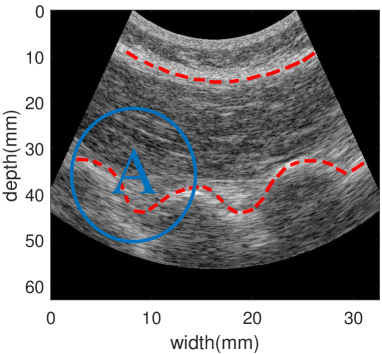

Figure 8 shows B-Mode image of the multifidus muscle, which is delineated by dashed red lines. Figures 9 a-b show the displacement fields estimated with NCC and STNCC with 70%percent7070\% overlap between windows. Figure 9 and Table 4 demonstrate that STNCC calculates a superior displacement field compared to NCC.

Refer to caption

Figure 8: B-mode image of the back muscle. Red dashed lines delineate the multifidus muscle. Visual inspection of the B-mode images shows the maximum displacement occurring in the region marked with the letter A.